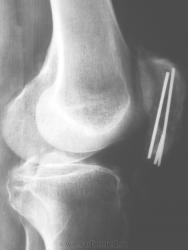

Пол пациента: Мужской пол Тип патологии: Травма Область исследования: Скелетно-мышечная система Методы исследования: Rg После операции. И так бывает, пациент жалоб не предъявляет https://radiomed.ru/sites/default/files/styles/case_slider_image/public/user/6152/2000.jpg?itok=kpUbJZyq https://radiomed.ru/sites/default/files/styles/case_slider_image/public/user/6152/2002.jpg?itok=ekIs4rwy https://radiomed.ru/sites/default/files/styles/case_slider_image/public/user/6152/2003.jpg?itok=G7ZQHQ9V ID:7928 Втр, 12/10/2010 - 14:10 #1 Александр Викторович Не на сайте Был на сайте: 8 лет 2 дня назад Зарегистрирован: 31.07.2010 - 13:05 Публикации: 639 летать будет проблематично, в смысле авиаперелетов... Втр, 12/10/2010 - 20:53 #2 stovbav Не на сайте Был на сайте: 2 года 2 месяцев назад Зарегистрирован: 20.12.2009 - 17:28 Публикации: 7066 Раз жизнь "обломала" то и травматологи не стали ей перечить, пошли тем же путем, да, очевидно, и правильно сделали. Болезни ног: виды, симптомы, причины, профилактика и лечение